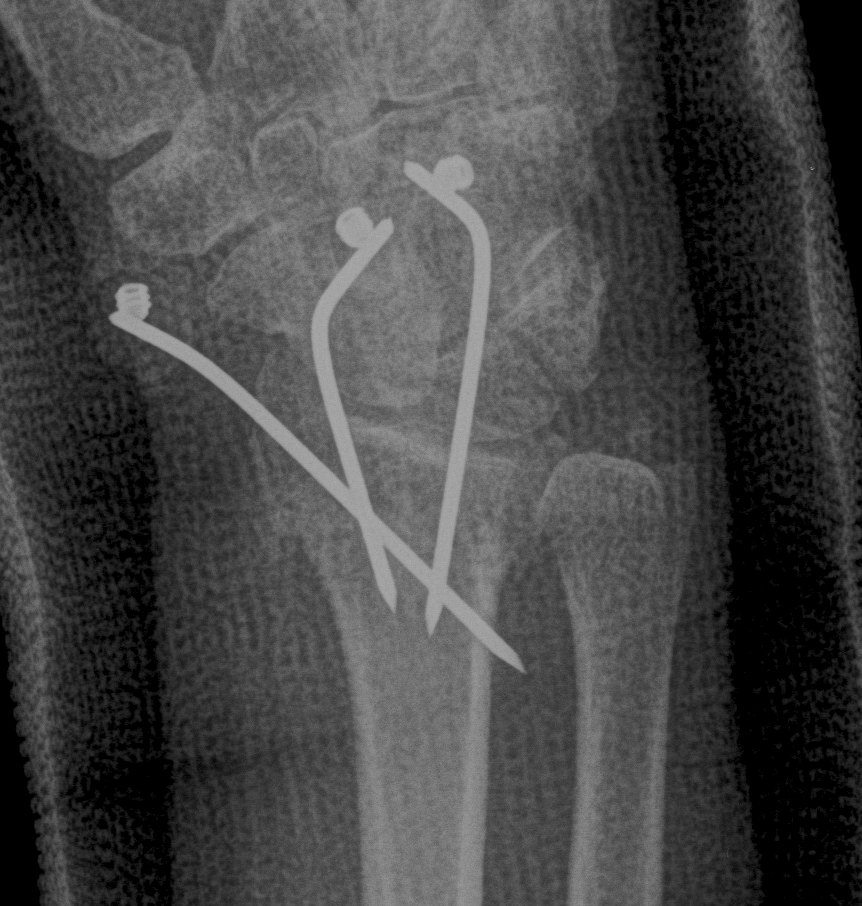

Surgical options

K wires

Distal Radius Fracture K wires APplateex fixbridge plate